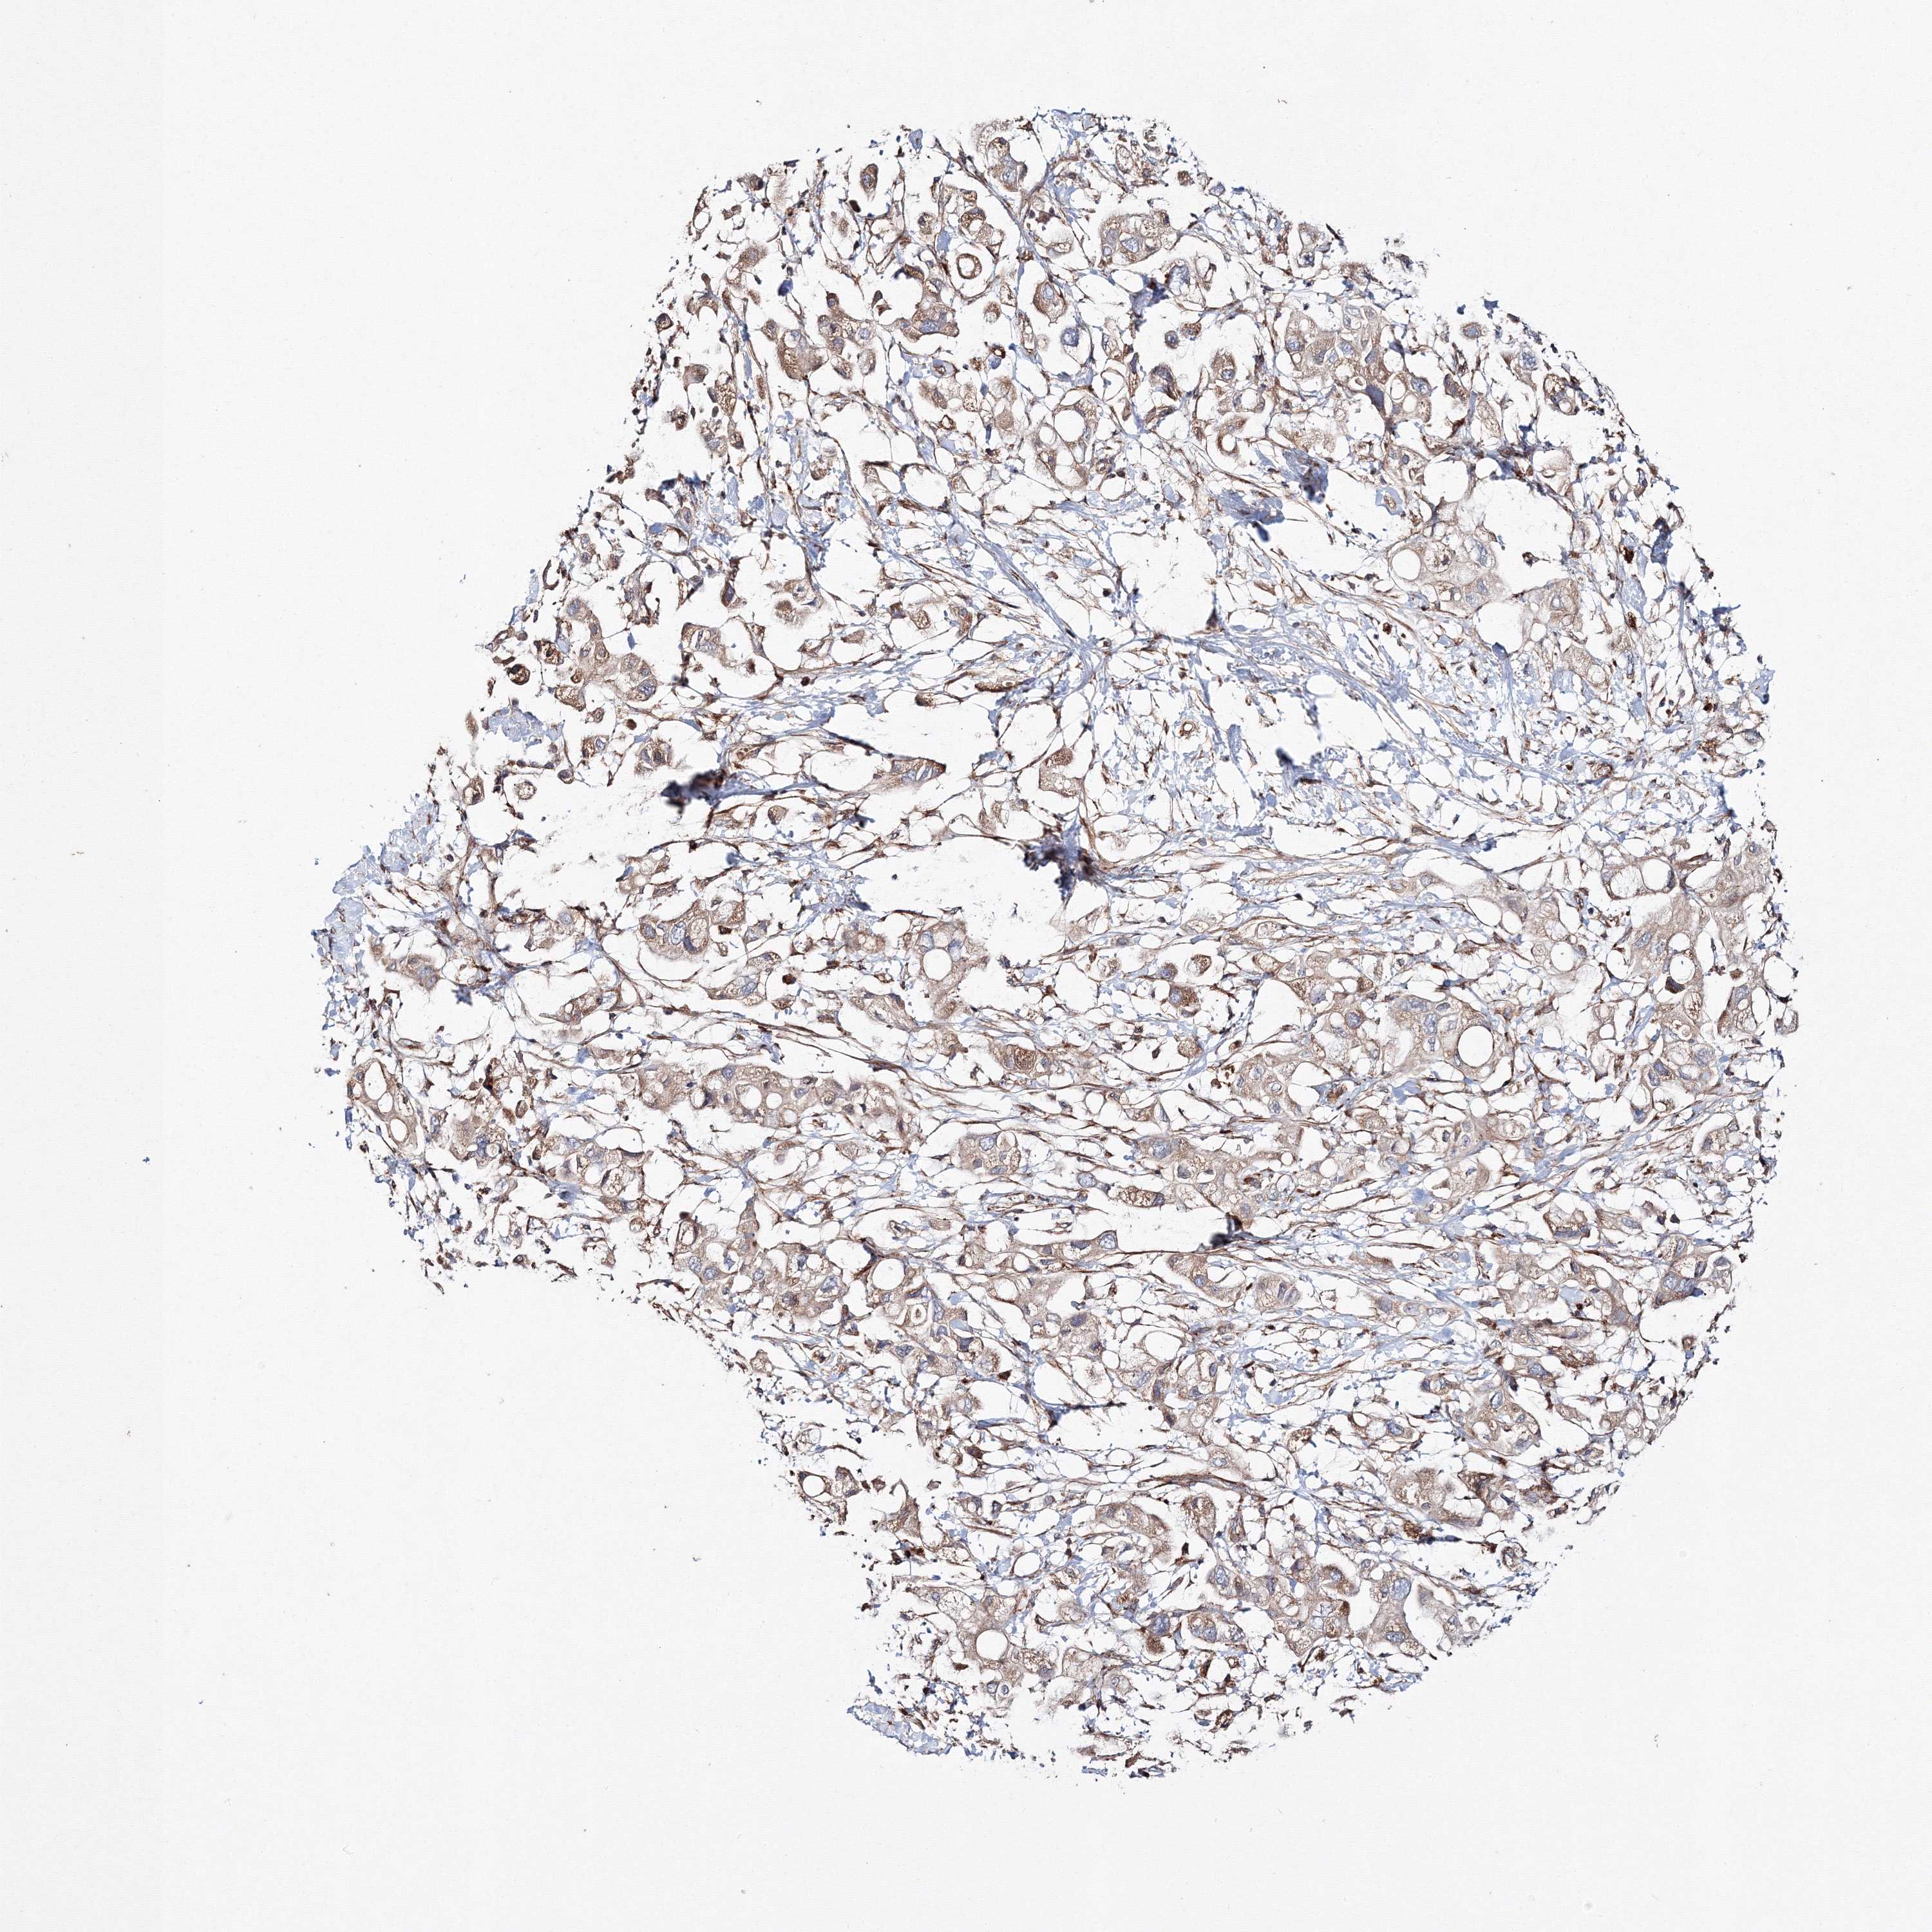

PANCREATIC CANCER - Protein expressioni

A mouse-over function shows sample information and annotation data. Click on an image to view it in a full screen mode. Samples can be filtered based on level of antibody staining by selecting one or several of the following categories: high, medium, low and not detected. The assay and annotation is described here.

Note that samples used for immunohistochemistry by the Human Protein Atlas do not correspond to samples in the TCGA dataset.

Antibody stainingi

Antibody staining in the annotated cell types in the current human tissue is reported as not detected, low, medium, or high, based on conventional immunohistochemistry profiling in selected tissues. This score is based on the combination of the staining intensity and fraction of stained cells.

Each image is clickable and will lead to virtual microscopy that enables deeper exploration of all samples and also displays staining intensity scores, fraction scores and subcellular localization as well as patient and tissue information for each sample.

Antibody HPA037525

Antibody HPA037526

Staining

High

Medium

Low

Not detected

Intensity

Strong

Moderate

Weak

Negative

Quantity

>75%

75%-25%

<25%

None

Location

Nuclear

Cytoplasmic/membranous

Cytoplasmic/membranous,nuclear

Adenocarcinoma, NOS